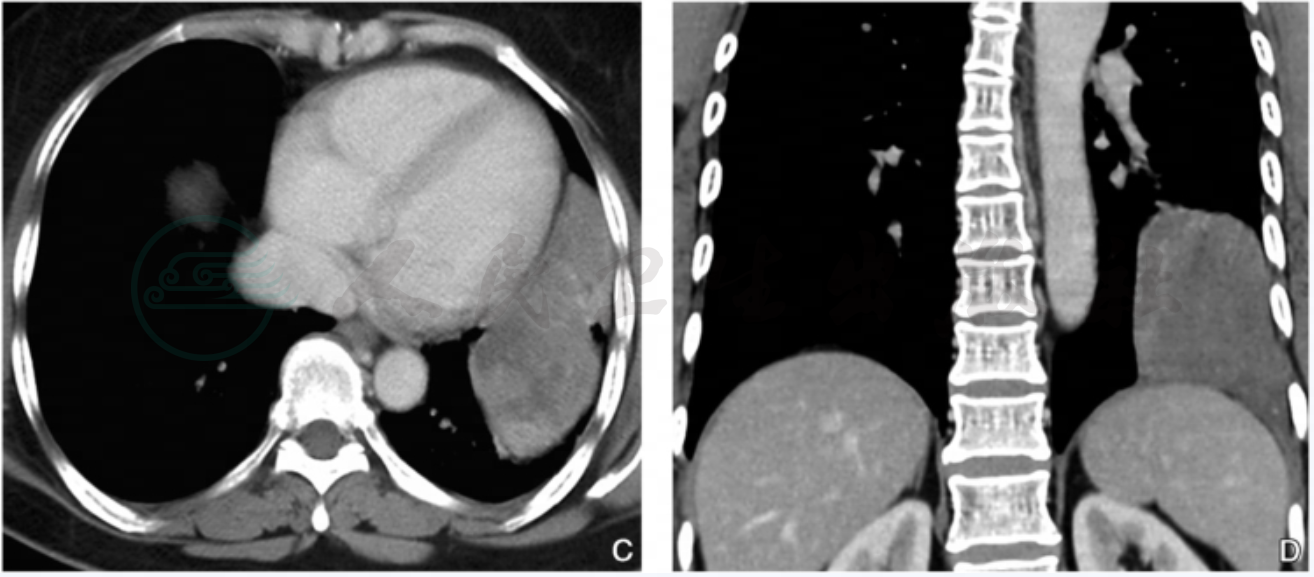

图2 膈肌转移瘤(恶性胸腺瘤)

注:男性,58岁,CT横断面图像(A)示左侧膈肌弥漫性增厚并可见软组织肿块形成,密度尚均匀,邻近脾脏受压向内侧移位;冠状位(B)及矢状位(C)重建图像示左侧膈肌及左侧胸膜均可见弥漫不均匀增厚,左侧膈肌形态不规则,可见局灶性结节状突起,脾脏受压向下移位。